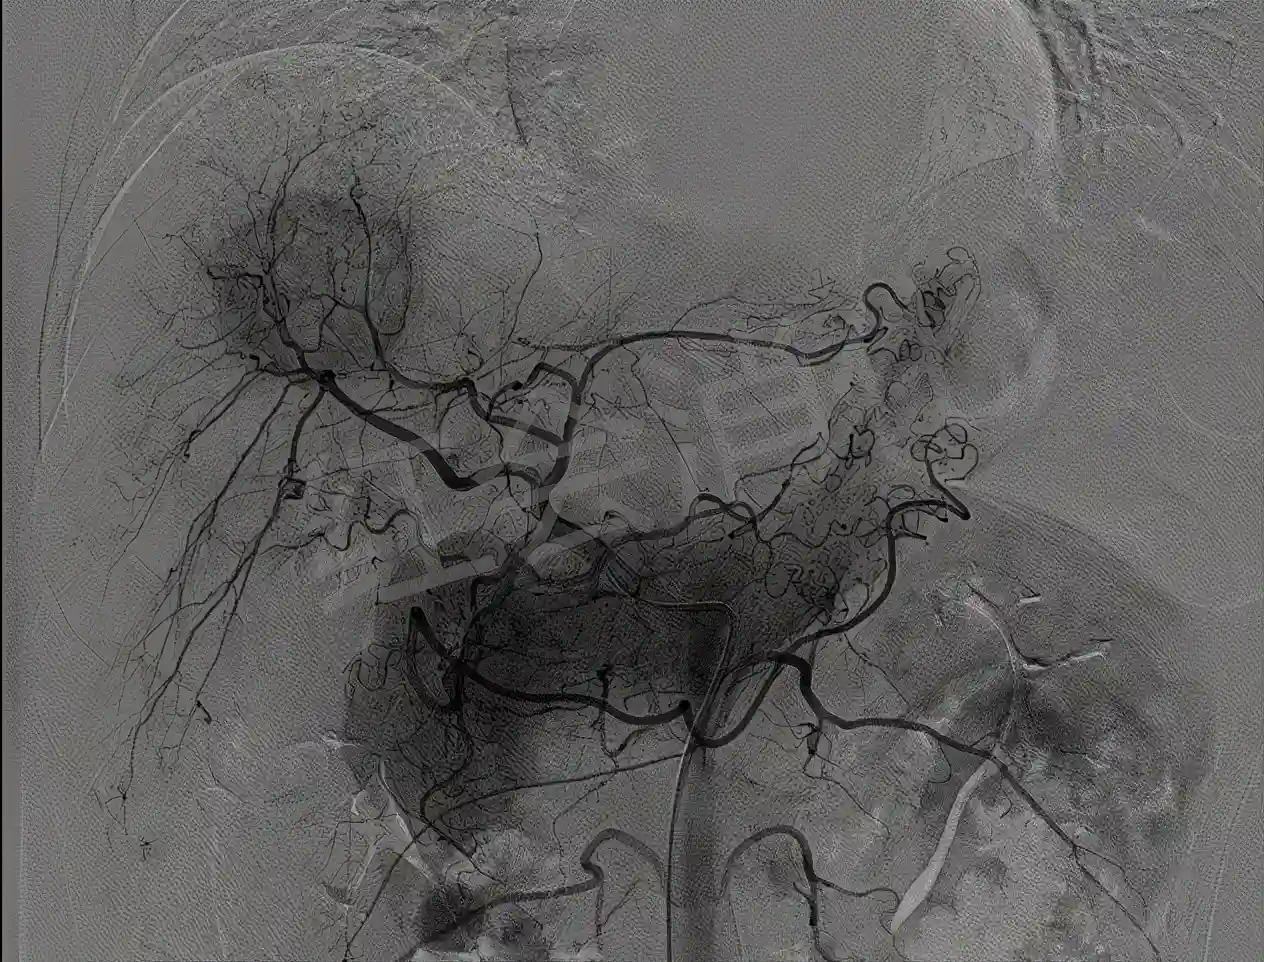

腹主动脉造影,明确肝动脉位置

栓塞前肝动脉造影,可见明显的动脉丛,成“球形”包绕

超选肿瘤供血动脉造影,可见肿瘤染色明显,予以灌注化疗栓塞治疗

栓塞后肝动脉造影,肿瘤周围的动脉丛消失,动脉化疗栓塞成功